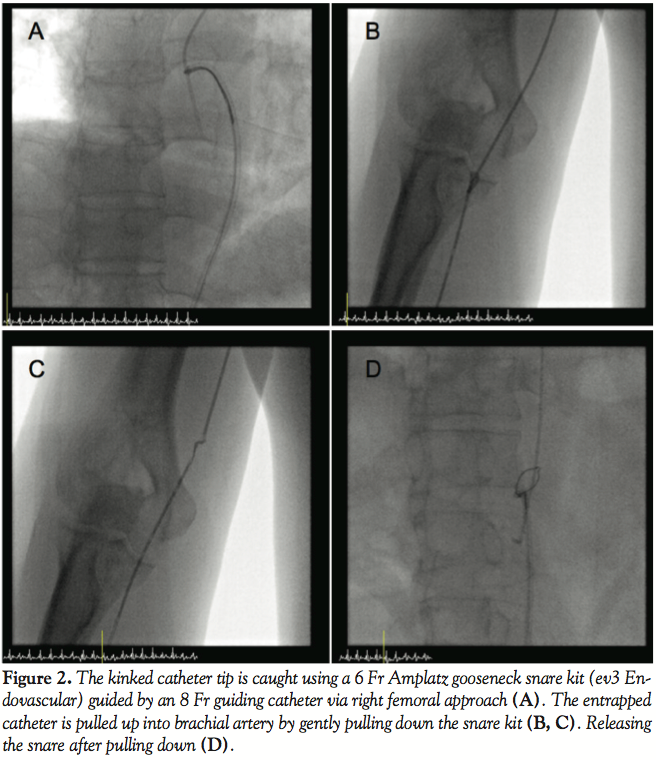

radial artery. Attempts to unravel the catheter with gentle rotation caused severe forearm pain. After femoral artery puncture, anterograde brachial angiogram confirmed the position of entrapped catheter within the radial artery (Figure 1D). Transfemoral coronary angiogram showed severe stenosis involving the left anterior descending artery (LAD). To avoid possible injury of aortic valve or coronary ostium during manipulation of the retrieval device, the entrapped catheter was pulled down into descending aorta using 8 Fr JL4 guiding catheter. The kinked catheter tip was caught using a 6 Fr Amplatz GooseNeck Snare Kit (ev3, Inc.) guided by an 8 Fr guiding catheter via a right femoral approach (Figure 2A). While gently pulling down the snare kit, the entrapped catheter was pulled up into the brachial artery (Figures 2B and 2C). After releasing the snare (Figure 2D), the kinked catheter was unraveled with a .35 inch J-wire and successfully removed through the radial sheath. After removal, percutaneous coronary intervention of the LAD was performed successfully using 2 stents (Figures 3A and 3B). The patient had an uneventful recovery and was discharged on the following day.